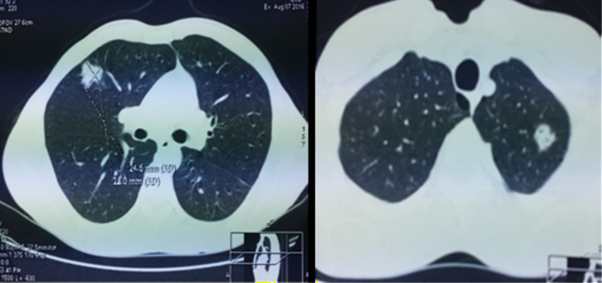

Figure

2: tdm thoracique: multiple bilateral

pulmonary nodules ecaves, emphysemous lung.

On the pulmonary plane, computed tomography finds peripheral nodular condensations of variable size, sometimes excavated, corresponding to disseminated septic embolus. Pleural effusions or pneumothorax are common. The effect on respiratory function may be minimal as in our observation or become much more severe with acute respiratory distress syndrome leading to assisted ventilation.